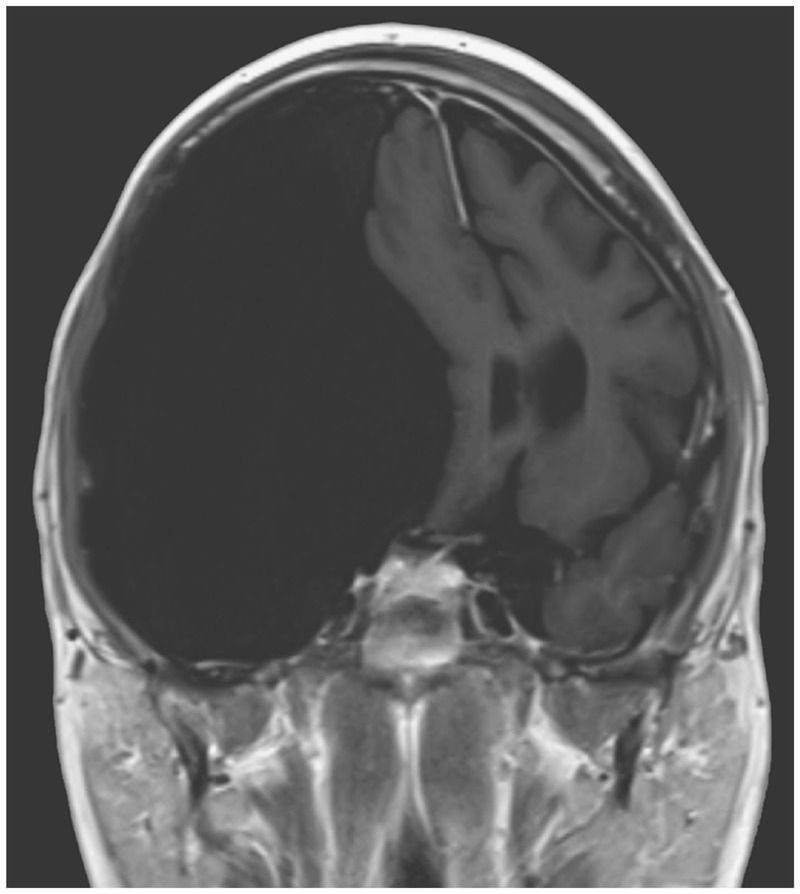

A 27-year-old man presented to the emergency department after a first seizure. He reported that during the previous 3 years, he had had frequent headaches and falls. Magnetic resonance imaging of the brain revealed an arachnoid cyst, measuring 12.3 cm by 16.5 cm by 7.9 cm, with mass effect on the right cerebral hemisphere; the cyst was causing displacement of the temporal lobe superiorly and posteriorly and a shift of midline structures. Arachnoid cysts are congenital malformations and are filled with cerebrospinal fluid, and they can be incidental findings on imaging. When large, as in this patient, they can cause a mass effect. A craniotomy for fenestration of the arachnoid cyst was performed; subsequently, a right frontal cyst-peritoneal shunt was placed because of persistently elevated intracranial pressure. Repeat imaging after these interventions revealed no substantial change in the size of the cyst. The patient continues to have daily headaches, and antiepileptic therapy has been prescribed to prevent additional seizures.